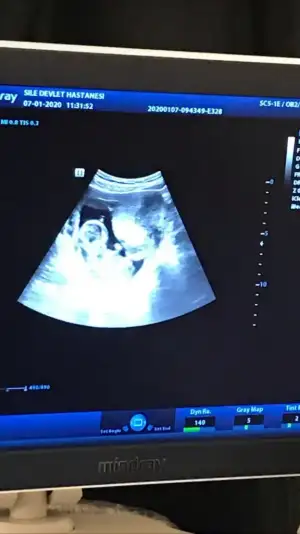

Haftam yaklaştıkça bir merak sardı.

O gözüken nub mu emin olamadım ama yine de bir atayım belki fikir yürüten olur didimm.

10+5 günlük bir kurbağa 🐸 🐣

Ne dersiniz?? Ikra meyra Ikra meyra